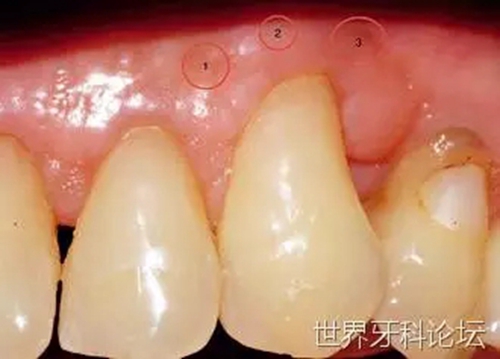

一位41歲男性患者,下前牙嚴(yán)重的創(chuàng)傷性牙齦退縮。經(jīng)過(guò)仔細(xì)咨詢后,患者預(yù)約進(jìn)行膜齦手術(shù)(圖8)。因缺少角化牙齦且前庭溝淺,唯一的治療方法是進(jìn)行游離牙齦移植以覆蓋根面。

圖8:膜齦手術(shù)前。

在受區(qū)翻起半厚瓣,去除所有上皮部分(圖9)。移植的牙齦組織緊密縫合于受區(qū),避免形成厚的滲出層,使最終結(jié)果受到影響(圖10)。

圖9:受區(qū)預(yù)備。

圖10:固定移植物后,激光照射位點(diǎn)。

術(shù)后 14天內(nèi),使用平頭手機(jī)以MSP模式、10Hz、0.5W(LightWalkerATS, Fotona, Ljubljana, Slovenia)、60s秒每位點(diǎn),每隔一天進(jìn)行生物調(diào)節(jié)(七次)。在術(shù)后14天(圖11)及整個(gè)42天愈合期(圖12)內(nèi),移植成功,根面得到覆蓋。